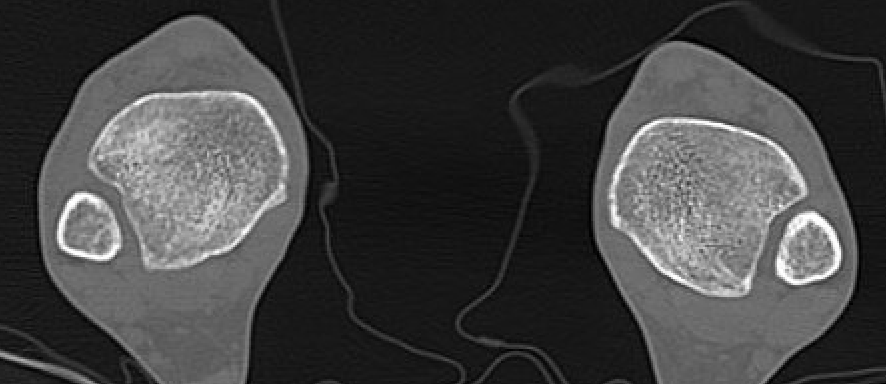

CT

Normal bilateral axial CT

Bilateral axial CT

- compare to other side

- widening

- malrotation

- posterior malleolar fracture / Volkmann tubercle

- anterior tubercle / Tillaux-Chaput tubercle

Gifford's tibiofibular line (TFL)

- anterolateral fibula

- should be < 2 mm from tibia

< 4 mm Tibio-fibular gap

Normal Gifford's line and tibiofibular gap

Abormal Gifford's line and increased tibiofibular gap with posterior malleolar fracture

Tillaux-Chaput fracture on right with mild increased widening